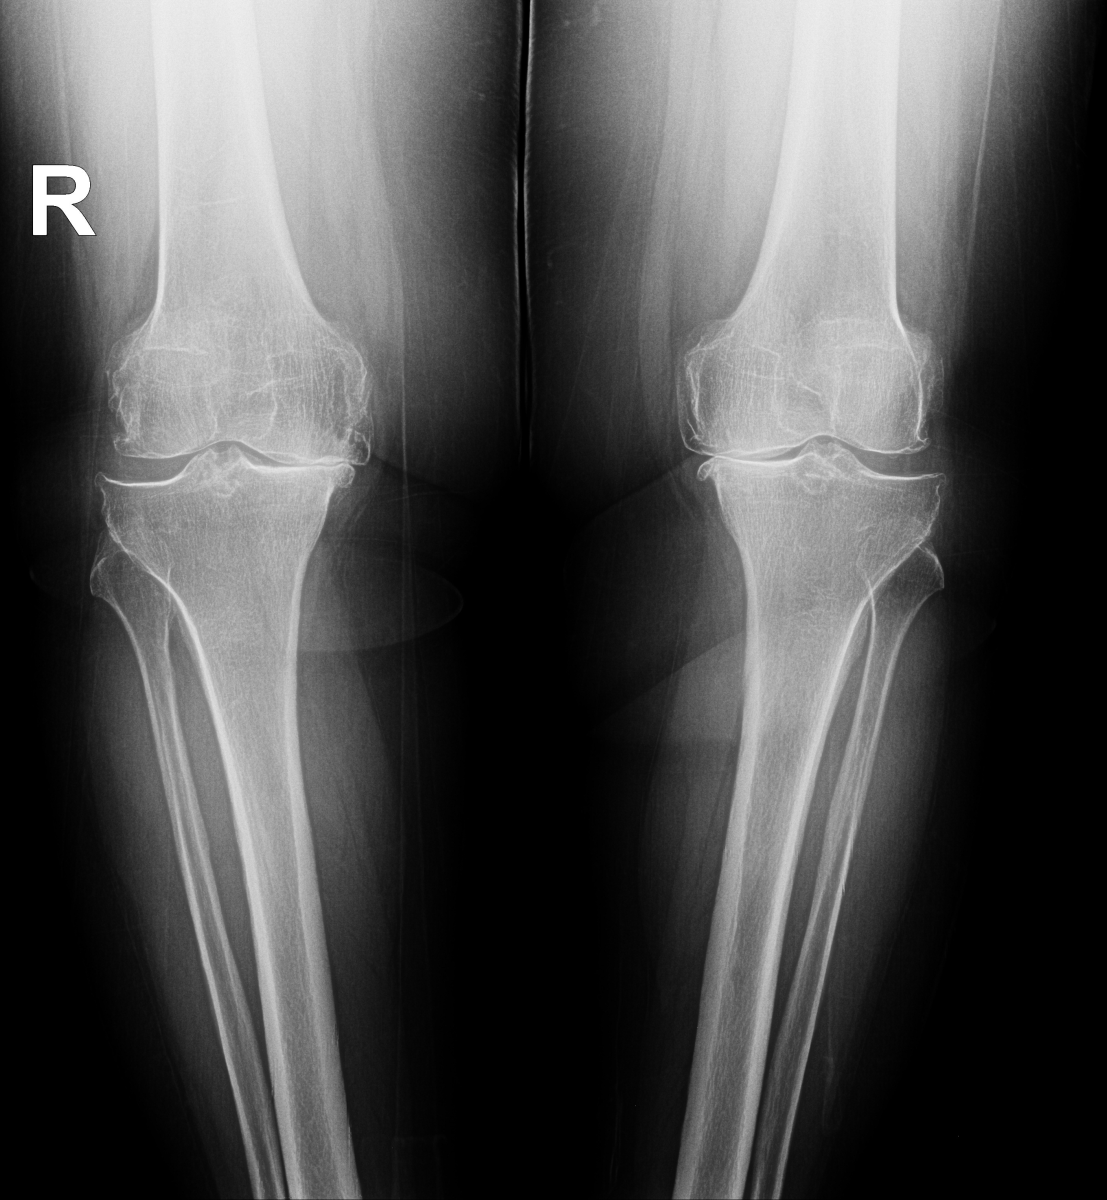

Bilateral gonartrozlu hasta grafisi

Dizin iç kısmında kıkırdak incelmiş ve buna bağlı olarak eklem aralığı daralmış.